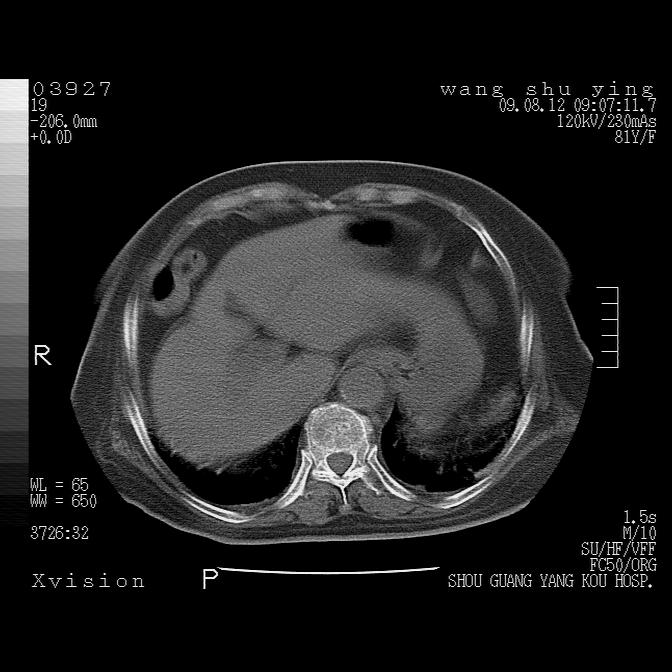

以下是引用随光逐影在2009-8-12 19:42:00的发言:[br]1)两肺感染性病变伴双侧胸膜肥厚。2)不排除左侧甲状腺腺瘤。3)肝脏占位性病变;建议行进一步检查。